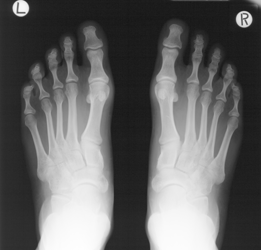

LHSA has used substitution to address the risks associated with cellulose nitrate and poor condition cellulose acetate x-radiographs in the collections.

Case study: background LHSA collections include c.20,000 x-rays originally on cellulose acetate, cellulose nitrate and polyester film base. They relate to hospitals in the Lothian region and to series of patient case notes held. Serious concerns regarding the x-rays in their original format were identified including low potential usage due to limited available cataloguing, the inappropriate and inefficient current storage system, and the degraded – and, in the case of nitrate film, flammable – nature. The condition of the film-based x-rays also posed health and safety risk to the staff and the potential to accelerate deterioration of paper-based collections held in the same storage area.

Cold storage for the whole x-ray collection was not a realistic and sustainable long-term solution for the volume and condition of the x-rays held and the decision to digitise and dispose as appropriate was carefully taken. A small collection of x-rays (relating to the Dott case notes) to serve as a reference sample and any x-rays too fragile to undergo the digitisation process have been preserved in cold storage.

Case study: treatment Liaison with Transmedia Technology Limited, who had previously digitised LHSA’s historic microfilm, determined the scanning parameters. Professor Jonathan Best, Radiologist, acted as a consultant to ensure that no medical information was lost in the digital version. The x-rays have been scanned at 300dpi, 16 bit and saved as TIFs on master and copy DVDs. Work to accompany digitisation included assigning a unique ‘X’ number to the x-rays for a given patient, packaging and labelling the x-rays for transit and scanning, compiling an Excel spreadsheet to enable future access to the collection, and a comprehensive quality control check of the substitutes produced.

Case study: conclusion The work to digitise the x-ray collection was an ambitious project, which, through successful execution, has met the preservation needs of both the x-rays and the paper-based collection items in the Archive. Investigation into means to promote use and the need for any future migration of data to ensure long-term accessibility to LHSA’s digital assets is ongoing and led by the Assistant Archivist.